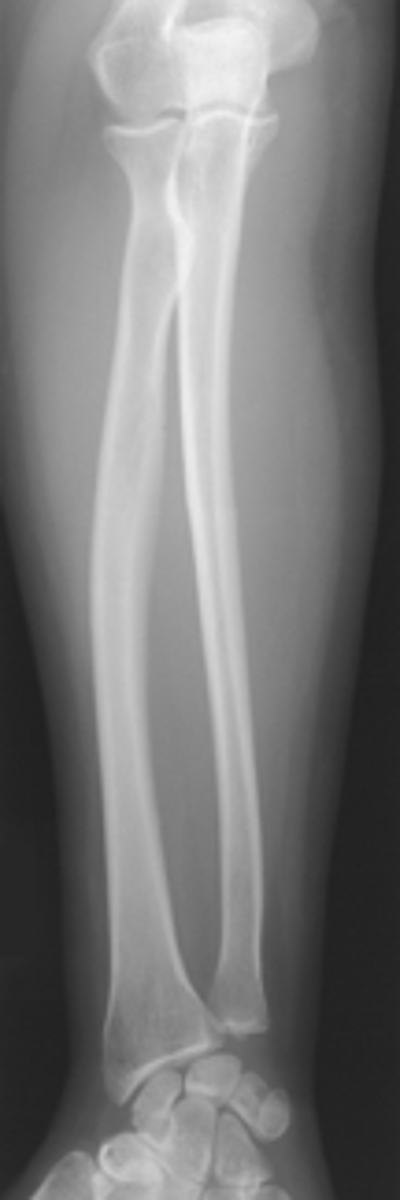

AP forearm

Lateral forearm

pronator fat stripe